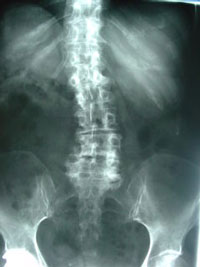

Well, that is not completely true. Poulin Chiropractic of Herndon and Ashburn treats many Ashburn and Herndon older patients with scoliosis and helps soothe their pain with chiropractic. Scoliosis (a curvature of the spine) can develop in the young years of life and then get worse OR begin disc degeneration and pinched nerves in the middle back and lower back. The pinched nerves are caused by a condition called spinal stenosis (a narrowing of the nerve opening spaces in the spine). Now, the condition of scoliosis and disc degeneration may cause pain in the legs due to stenosis. Pain down the legs called sciatica is caused by a specific pinched nerve. But chiropractic can help!

Spinal stenosis in older adults with scoliosis is prevalent in our chiropractic, so you’re not a unique case! As a matter of fact, one study of 36 patients with a mean age of 69 years had leg pain at a severity level of 6.5 (on a scale of 0 no pain to 10 the worst pain the patient had ever had). 97% of these patients also showed at least one level of severe stenosis, and all but one had severe leg pain, too. (1) Your Ashburn and Herndon chiropractor at Poulin Chiropractic of Herndon and Ashburn is trained and ready to advise you on an effective stenosis and scoliosis treatment plan to gain pain relief.